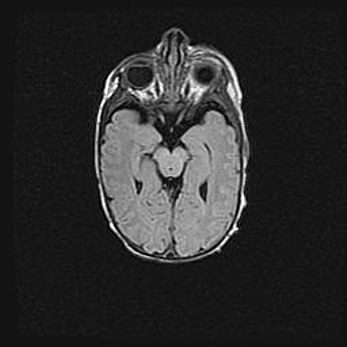

Множественные кисты обоих полушарий головного мозга, наибольшая из них в правой затылочной области. Ассиметричная атрофическая гидроцефалия.

Возраст: 7 месяцев

Вес: 5660 г

Пол: мужской

Окружность головы: 41,5 см

Срок гестации: 28-29 недель

Кисты головного мозга развиваются в результате многоочаговых некрозов вещества мозга и возникают вследствие перенесенной перинатальной инфекции, менингитов, энцефалитов, асфиксии, родовой травмы, расстройств мозгового кровообращения различного генеза. Образованию кист в веществе головного мозга плодов и новорожденных способствуют такие факторы, как высокое содержание в нем воды, недостаточная (или отсутствие) миелинизация и слабая астроглиальная реакция на повреждение.

Кисты могут сочетаться с гидроцефалией и другими поражениями головного мозга.